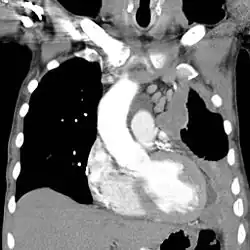

The most common diseases associated with chronic asbestos exposure are asbestosis (scarring of the lungs due to asbestos inhalation) and mesothelioma (cancer associated with asbestos).[10] Mesothelioma is an aggressive form of cancer and often leads to a life expectancy of less than 12 months after diagnosis.[118]

All types of asbestos fibers are known to represent serious health hazards in humans and animals.[119][120][121] Amosite and crocidolite are considered the most hazardous asbestos fiber types;[122][123] however, chrysotile asbestos has also produced tumors in animals and is a recognized cause of asbestosis and malignant mesothelioma in humans,[124] and mesothelioma has been observed in people who were occupationally exposed to chrysotile, family members of the occupationally exposed, and residents who lived close to asbestos factories and mines.[125]